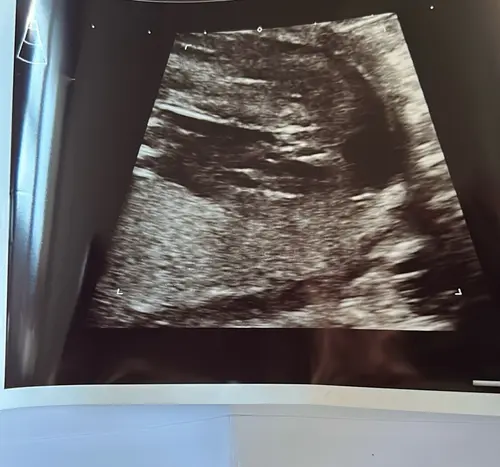

Ik bedoelde dit; het oranje is het halve rondje wat ik bedoelde ( had het idee dat dit van bovenaf de heupen/ bekken zouden zijn?)

En het gele als je inzoomt zie je duidelijk de streepjes